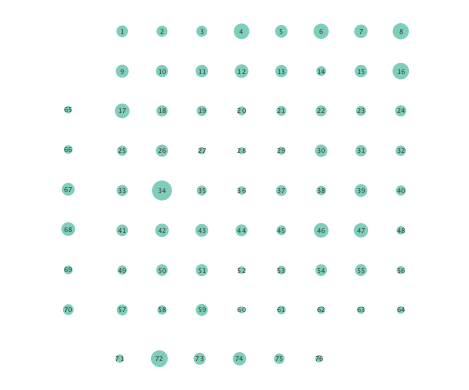

Figure 2 depicts networks inferred from different algorithms for both preictal and ictal intervals of the time series. The figure illustrates results obtained by the linear SVARM, and the K-SVARM approach with and without kernel selection. Each node in the network is representative of an electrode, and it is depicted as a circle, while the node arrangement is forced to remain consistent across the four visual representations. A cursory inspection of the visual maps reveals significant variations in connectivity patterns between ictal and preictal intervals for both models. Specifically, networks inferred via the K-SVARMs, reveal a global decrease in the number of links emanating from each node, while those inferred via the linear model depict increases and decreases in links connected to different nodes. Interestingly, the K-SVARM with kernel selection recovered most of the edges inferred by the linear and the K-SVARM using a polynomial kernel, which implies that both linear and nonlinear interactions may exist in brain networks. Clearly, one is unlikely to gain much insight only by visual inspection of the network topologies. To further analyze differences between inferred networks from both models, and to assess the potential benefits gained by adopting the novel scheme, several network topology metrics are computed and compared in the next subsection.

First, in- and out-degree was computed for nodes in each of the inferred networks. Note that the in-degree of a node counts its number of incoming edges, while the out-degree counts the number of out-going edges. The total degree per node sums the in- and out-degrees, and is indicative of how well-connected a given node is. Figure 3 depicts nodes in the network and their total degrees encoded by the radii of circles associated with the nodes. As expected from the previous subsection, Figures 3 (a) and (b) demonstrate that the linear SVARM yields both increases and deceases in the inferred node degree. On the other hand, the nonlinear SVARM leads to a more spatially consistent observation with most nodes exhibiting a smaller degree after the onset of a seizure (see Figures 3 (c) and (d)), which may imply that causal dependencies thin out between regions of the brain once a seizure starts.